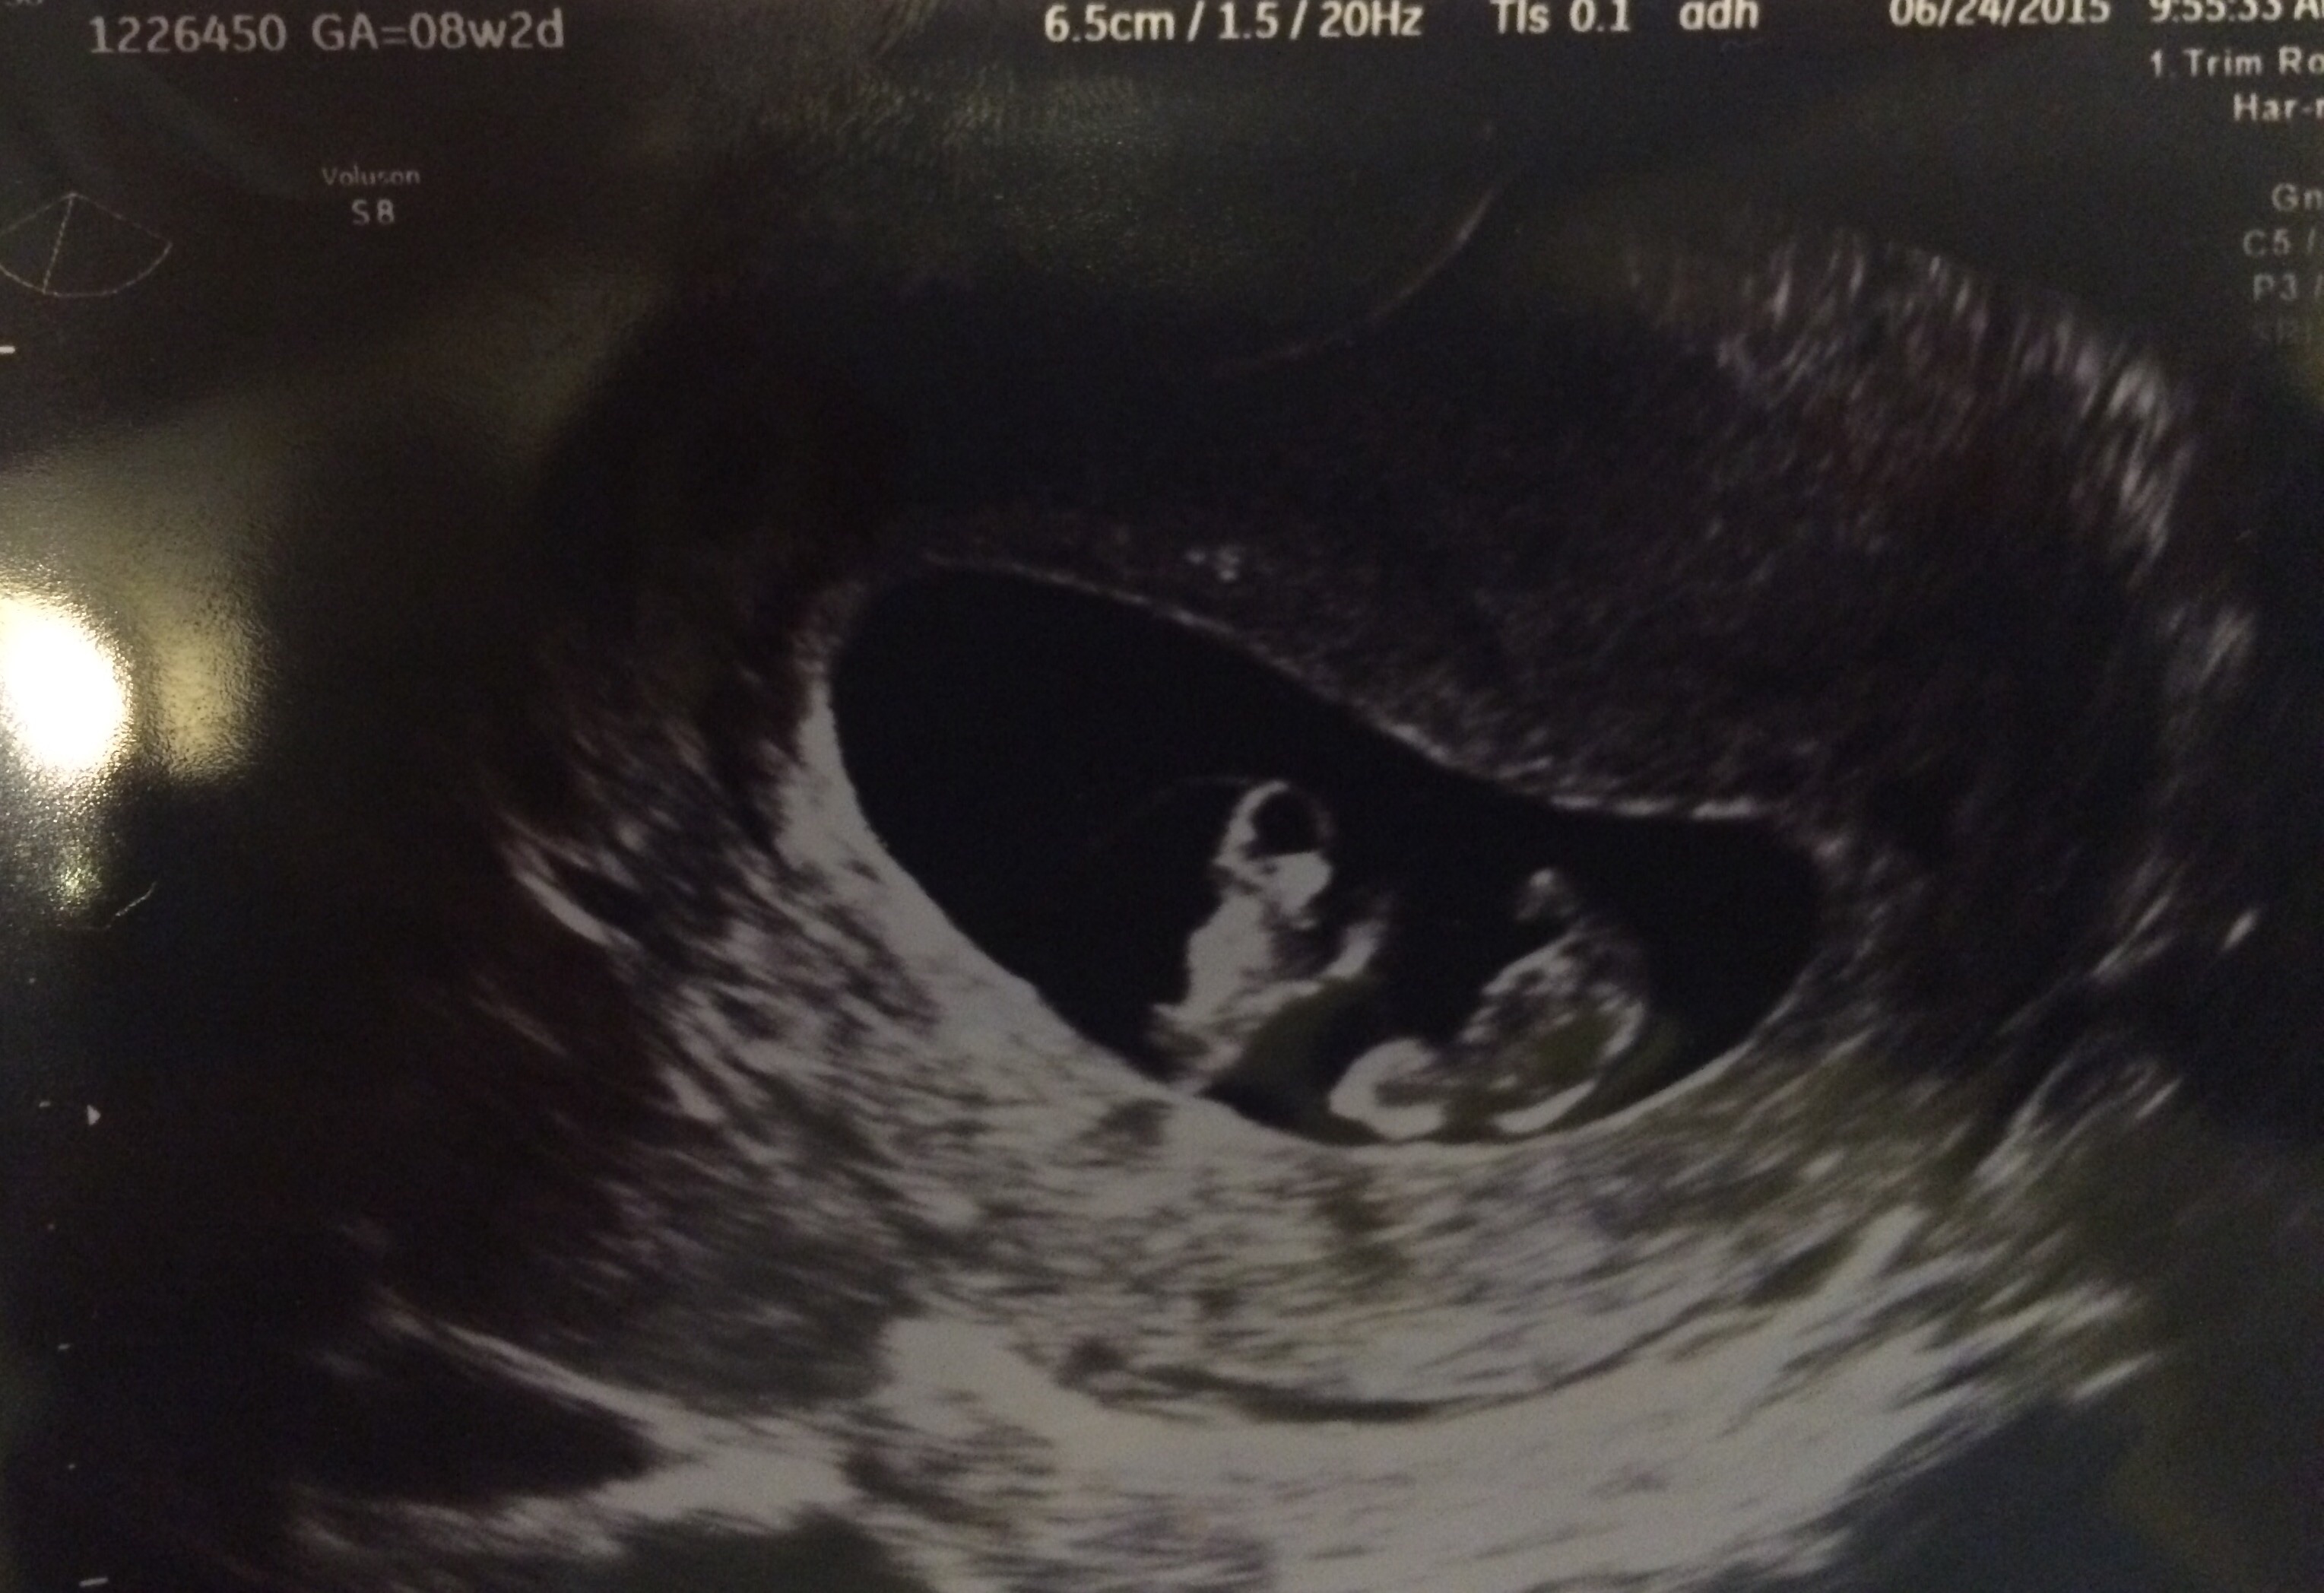

This was from August 3. Baby measured 9w6d (only 1 day behind) with a due date of 2/29/16. He/she was sleeping, so I didn't get to see any movement, but I have my 12 week NT scan in a couple weeks so I'm hoping to see some action then. My husband and I got to hear the heartbeat, which the doctor said sounded like it was in the 160's. I'm very relieved everything seems to be okay with this one after losing my first one at 7 weeks back in March. Lucky to get a second chance :-)